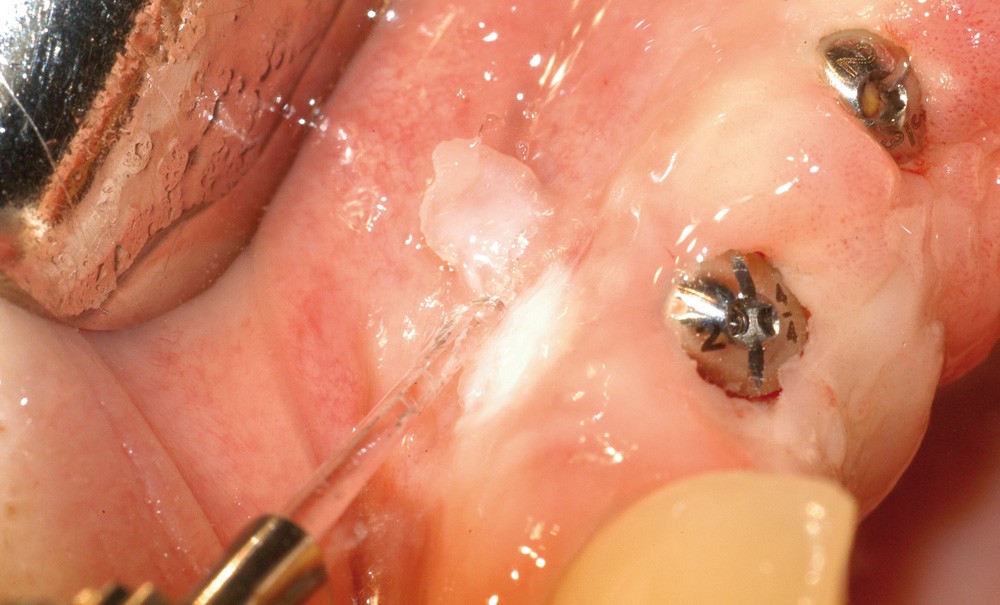

Parmi les différents lasers disponibles, le choix du laser Er:YAG s’explique par ses propriétés physiques et biologiques qui en font la longueur d’onde la plus polyvalente, la plus efficace et la plus sécurisante pour une utilisation en parodontie [1]. Cependant, les résultats cliniques dépendent de la précision de l’opérateur et du respect les protocoles. L’utilisation d’aides optiques apparaît indispensable (fig. 1).